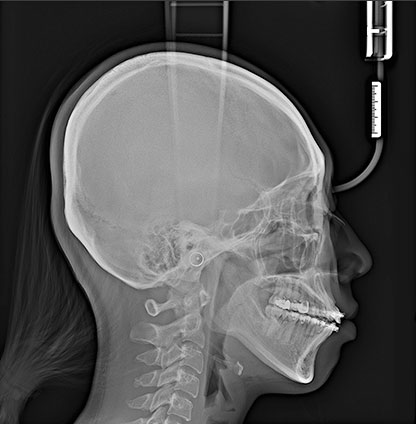

歯科用CTを用いた正確な診断

歯科用CTは、顎の骨の状態を3D画像で詳細に把握できる先進的な機器です。これにより、骨の厚さや密度を正確に確認でき、インプラント治療の計画をより精密に立てることができるため、治療の成功率を大幅に向上させます。

複雑な歯の根の状態も精密に診断できるため安全なインプラント治療に必須です。

シミュレーションソフトで事前確認

取得したCT画像をもとにシミュレーションソフトで治療計画を作成し、インプラントの埋入位置や角度を事前に確認します。このシミュレーションにより、手術の正確性が増し、歯茎を切開する範囲を最小限に抑えることが可能です。その結果、術後の治りが早まり、身体への負担も軽減されます。